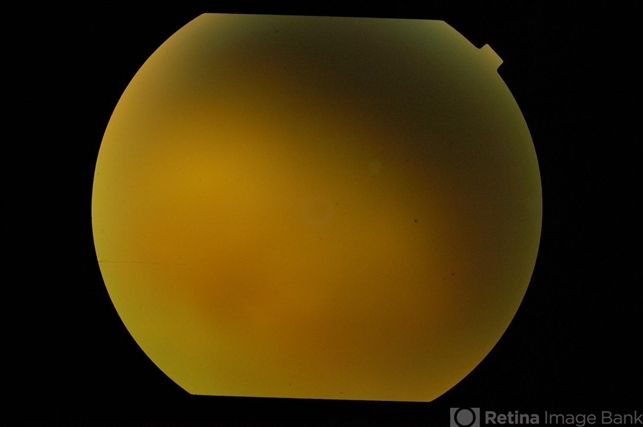

Fundus photograph of left eye of a 13-year-old boy with endogenous aspergillus endophthalmitis with retinal detachment and silicon oil in-situ 3 days after first presentation. Vitreous was hazy with inflammatory membrane over anterior surface of oil. Aspergillus was seen on smears and cultured from his vitreous. He had disseminated systemic aspergillus infection following use of oral steroids for nephrotic syndrome.